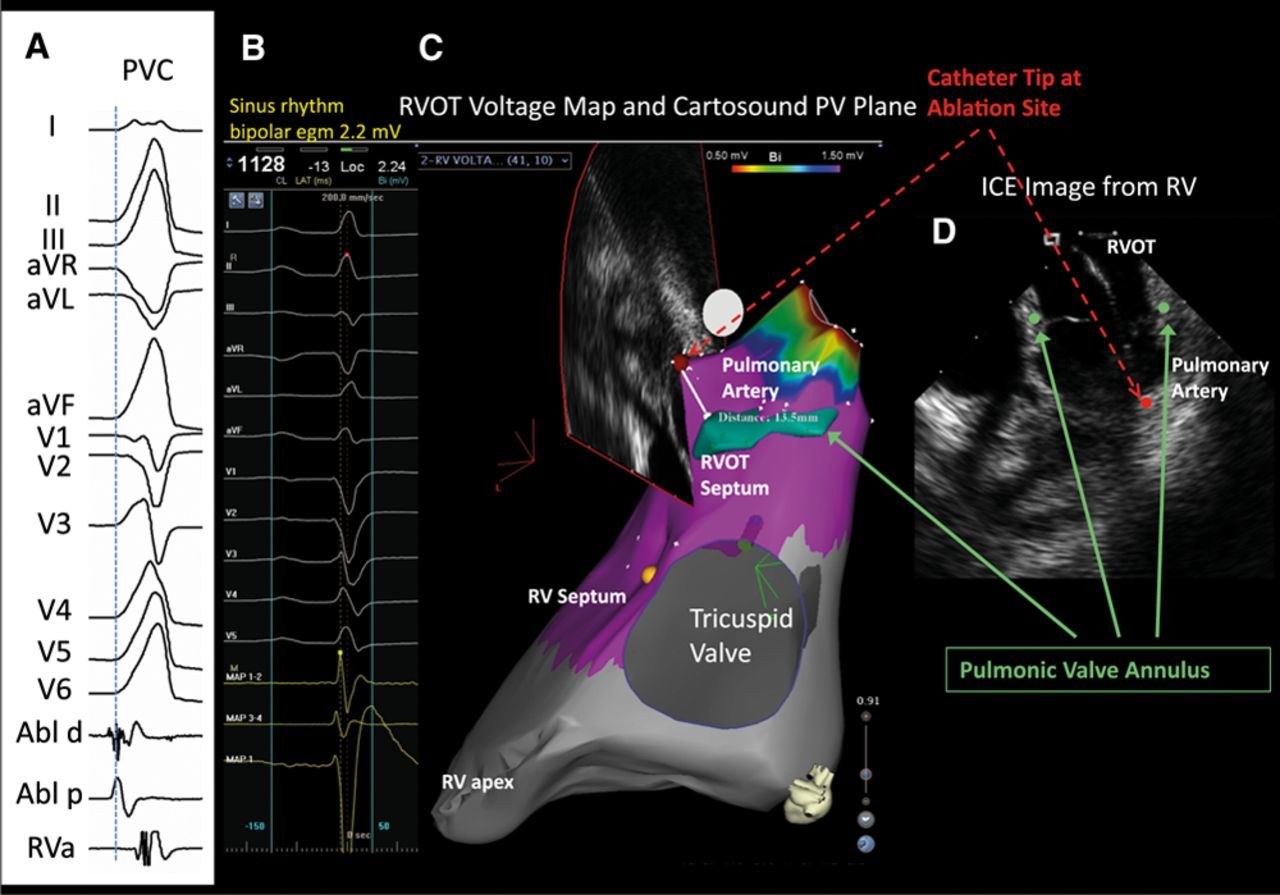

Supravalvar RVOT VT

• Most from close to pulmonary valve

• Can be above the pulmonary valve level (1)

Timmermans C, Rodriguez LM, Crijns HJ, Moorman AF, Wellens HJ. Idiopathic left bundle-branch block-shaped ventricular tachycardia may originate above the pulmonary valve. Circulation 2003; 108: 1960–1967.

Most PA-VAs missed (thought as RVOT)

pa_cartosound.jpg

Liu … Lerman. Ubiquitous Myocardial Extensions Into the Pulmonary Artery Demonstrated by Integrated Intracardiac Echocardiography and Electroanatomic Mapping. Circ Arrhythmia 2014;7:691-700.